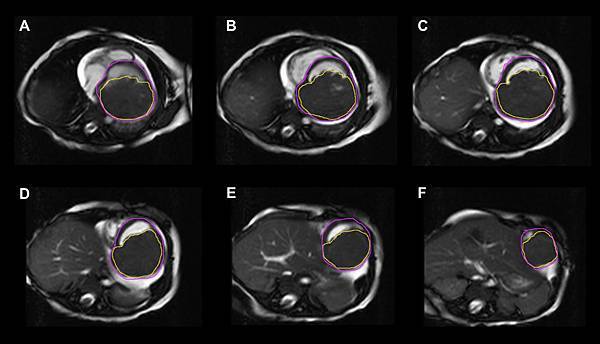

兒童時期擴張性心肌病變算是最難纏的心臟疾病之一。診斷心臟擴大並不難,難的是如何抽絲剝繭找出背後的病因。給予藥物治療並不難,難的是有沒有機會對症下藥。安排心臟移植的評估並不難,難的是能否找到可以不要換心的選項。

這裡整理了台大兒童心臟團隊過去10多年曾參與發表的論文,都是關於兒童時期擴張性心肌病變的研究。每篇論文,背後都代表著團隊為了改變這群孩子的命運所曾做過的努力。從論文的作者群中可以清楚看出,照顧這群兒童時期擴張性心肌病變需要跨團隊的整合與努力,特別是基因醫學的專家,以及心臟外科團隊,更扮演著關鍵的角色。